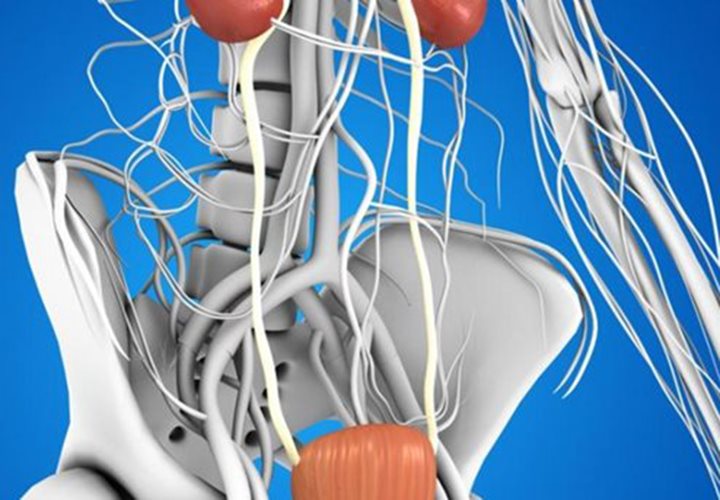

Suffering from an overactive bladder (OAB) can be troubling, disappointing and additionally humiliating. OAB alludes to an issue in the bladder that causes to contract before it is full, bringing about a sudden inclination to urinate, which could prompt the automatically loss of pee. With the right determination, OAB...